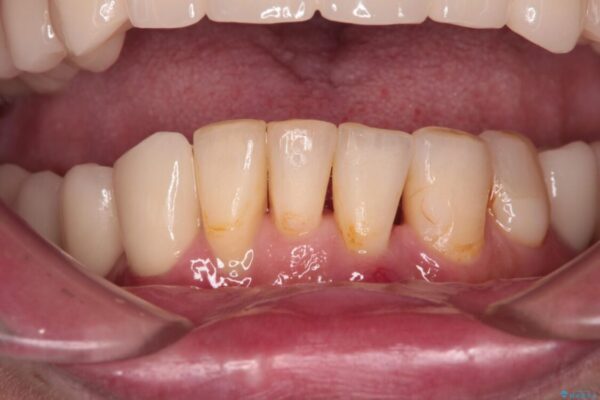

インプラント上の仮歯がボロボロになり、前歯に非常に負担のかかる状態であったため、早急に奥歯の仮歯を修復し、矯正治療、奥歯の補綴治療、前歯の補綴治療と順々に進めて行きました。

治療後

• 放置したインプラントとインビザライン 全顎リカバリー治療 治療後画像